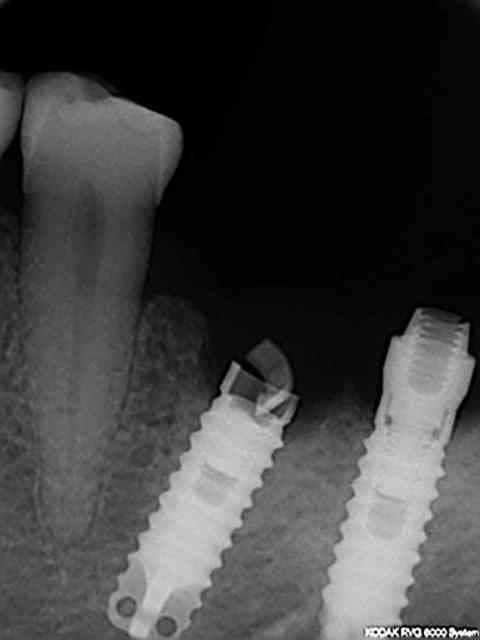

implant TBR posé en 1998 par confrère petit problème d'axe que j'avais temporairement résolu en utilisant prothèse transvissée .

en quelques mots

patiente

1)édentée bilaterale

2)bruxoman(girl)

3)suite implantaire difficile...n'a pas fait le travail de l'autre coté (à l'époque je faisais confiance et j'avais accepté de monter la prothèse)

4)la supra structure s'est dévissée deux fois en 7 ans et à chaque fois je la prévenais...

en regardant la rvg avec le col cassé on s'aperçoit que le filetage va bien plus loin que la vis donc j'ai présumé que je pourrai visser plus loin dans le fût.

modification du transfert:

en supprimant l'octogone du transfert totalement la vis va bien à fond (rvg jointe) mais par contre le transfert n'est pas en butée contre l'implant modifié donc j'ai modifié légèrement la vis pour qu'elle pousse le tansfert contre l'implant (ajout d'un petit anneau de duralay sur les premières spires ) de sorte qu'en vissant on soit bien en butée contre le fût (cf deuxième rvg)

puis j'ai controlé lors de l'essayage de l'armature que l'ensemble soit vraiment passif.

A priori ras mais ce cas n'a été possible que grace à la profondeur de filetage du fut .

A noter que la fracture du col vient aussi certainement du fait que les pièces usinés fabriquées n'appuyaient que sur la périphérie du col et ne venaient pas en butée sur le l'épaulement interne (contrairement au cone morse ou le principal de la force est dans la partie la plus épaisse) l'épaisseur étant à cet endroit. la partie la plus fine .